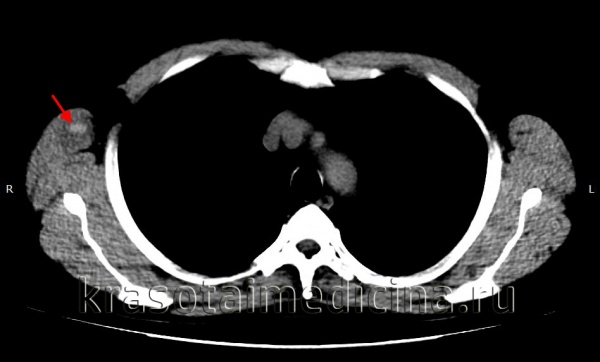

3. КТ при гематоме:

• На КТ видно асимметричное увеличение пораженной мышцы или тканевой плоскости:

о Обычно такой же плотности, что и мышца на неконтрастной КТ, но может быть более высокое поглощение в случаях с острым кровотечением

о Транформация в серому уменьшает поглощение

• Выход контраста из сосудов в гематому на контрастно-усиленной КТ свидетельствует об активном кровотечении

(Слева) На осевой неконтрастной КТ визуализируется опухолеподобная зона повышенного поглощения в большой ягодичной мышце у пожилого пациента после падения на область таза. На КТ снимке определяется острая гематома, если обратить внимание на незначительное повышение поглощения и облитерацию жировых полосок. Со временем поглощение гематомой снижается.

КТ ОГК. Гиперденсное скопление крови в толще мышечного массива грудной стенки справа, окруженное зоной отека.